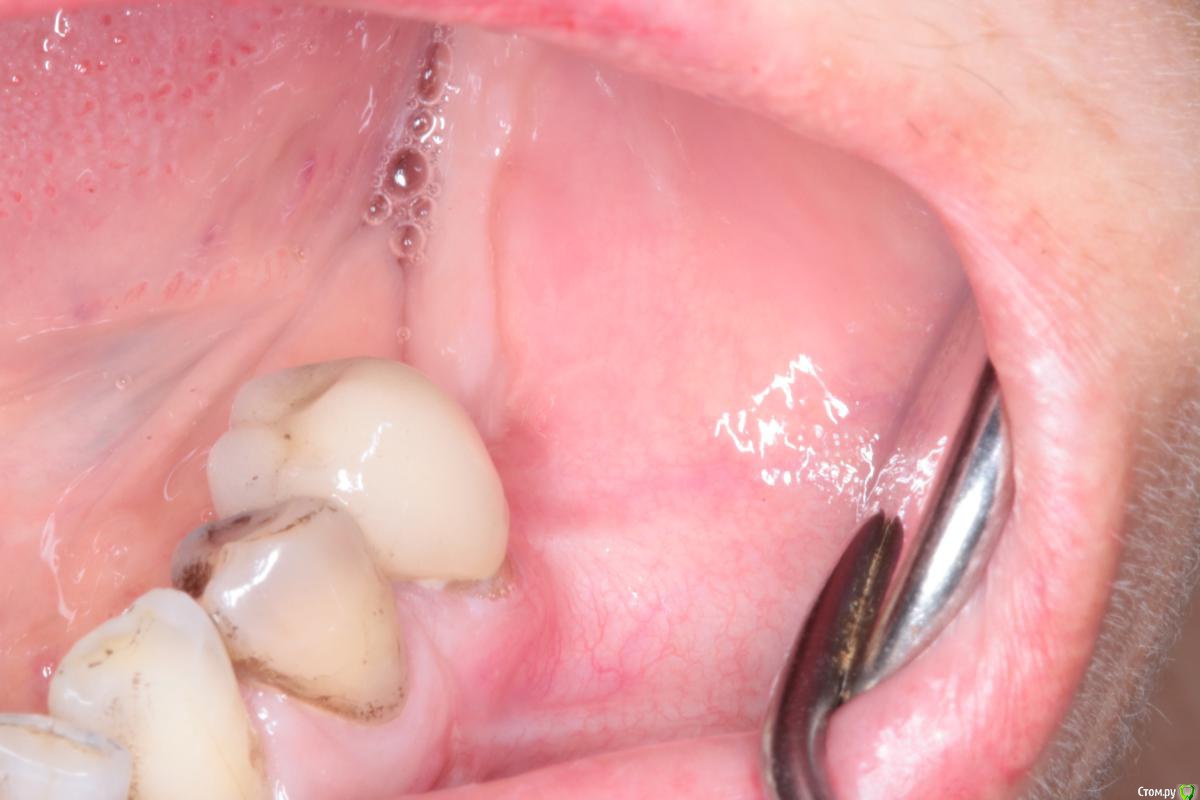

igorgergg Опубликовано 17 июня, 2018 Поделиться Опубликовано 17 июня, 2018 Всем привет, пациентке было сделано нкр в области 36 зуба с необиотековской сеткой. Щечный лоскут плохо натягивался после рассечения надкостницы и тупого прохождения ножницами и язычного отслаивания, пришлось сделать послабляющий между 4 и 5. Но и его не сильно хватило, лоскут язычно натягивался всего на 0.5 см где-то, чувствовал что натяжение есть.Хотя раньше, когда мобилизовался, хватало обычного рассечение надкостницы и язычно отслаиться. В итоге сетка прорезалась, но мне кажется есть и вторая причина почему, так как возможно на сетке были углы острые поэтому и не затянулась. Ушивался 2-3 П- образных и сверху простые узловые наглухо. Фото прилагаю. Сейчас хочу с мембраной эволюшен переделать, но есть опасения что причина также и в натяжении после ушивания, так как даже с послабляющим я не смог натянуть без натяжения лоскут. Также сейчас слизистая в этом месте подвижная и тонкая стала, что может усложнить операцию и ушивание. Чтобы был успех исключаю титановую сетку и вопрос в ушивании и также вопрос может пластику десны первым этапом сделать в такой ситуации (смещенным лоскутом с трансплантатом?), так как на этом месте сейчас щека натянута, на фото видно. Дайте плз обратную связь) Опыт есть, но его не так много Ссылка на комментарий

igorgergg Опубликовано 22 июня, 2018 Автор Поделиться Опубликовано 22 июня, 2018 Что за Pt на семёрке ?Тут с Эволюшн +2мм кости вестибулярного получить достаточно. Зачем сетки ?Имплант сразу.семерку удалили уже смущает тонкий биотип, думаю что сложно будет ушиться. в области пятеркки также прикрепенки не стало после нкр Ссылка на комментарий